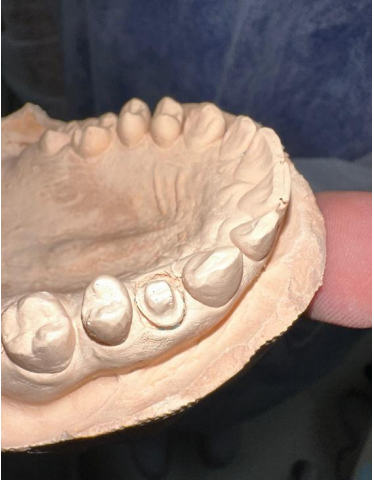

O modelo obtido a partir do molde e registro oclusal foram encaminhados ao laboratório protético, onde foi confeccionada a coroa de teste clínico e em seguida a definitiva em zircônia monolítica, de acordo com a cor e características anatômicas dos dentes adjacentes.

2ª Sessão: Foi realizada a prova clínica da coroa confeccionada pelo laboratório, sendo posicionado e avaliado quanto à adaptação marginal, pontos de contato proximais, e oclusão. Foram feitas pequenas adequações, para ajuste oclusal, e reencaminhada ao laboratório protético para o processo final da coroa.

Figura – Modelo funcional em gesso

Figura – Coroa para teste clínico